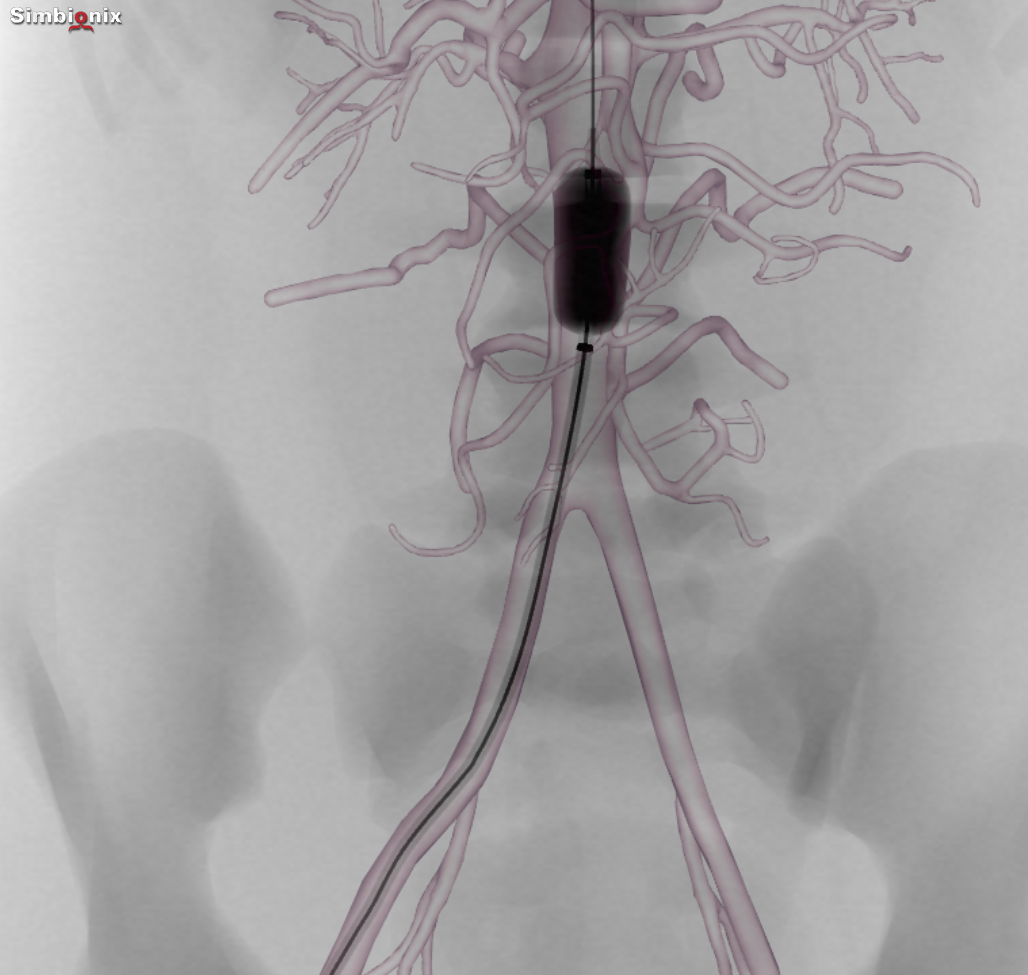

REBOA placement in zone III providing temporary aortic occlusion in the

REBOA placement in zone III providing temporary aortic occlusion in the How Does A Reboa Work resuscitative endovascular balloon occlusion of the aorta (reboa) has recently gained popularity as a minimally. resuscitative endovascular balloon occlusion of the aorta (reboa) is a minimally invasive technique using a balloon catheter to temporarily occlude the. The goal of reboa is to occlude blood flow to the major arterial vessel that is actively bleeding, and aortic insertion will. How Does A Reboa Work.